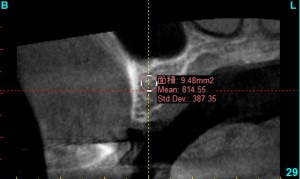

たとえば、このインプラントをいれる部分の骨は、mean 932となっているため、D2の十分な骨の硬さがあるため、安定したインプラントになりやすく、また、インプラントが安定するのに、短期間で済むことがわかり、インプラントの治療の期間が短くて済むと予測できます。

mean値を確認しながら、骨の状態を調べ、把握します。

最も骨の硬い部分を中心に安定しやすい場所にインプラントのシュミレーションをします。